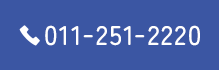

上顎前突の症例

初診時

治療終了時

治療終了時から2年経過時(保定開始時から2年経過時)

初診

治療終了時

治療終了後から2年経過時

(保定開始時から2年経過時)

| 年齢・性別 |

20代 女性 |

| 主訴 |

前歯が出ているのを治したい。 |

| 治療について |

上は前歯をかなり下げるために小臼歯、更に大臼歯を抜歯、下はガタガタを治すため、小臼歯の抜歯を行いました。 |

| 治療期間 |

2年 |

| 治療費用 |

1,310,100(検査料と診断料、全ての調整料を含みます) |

| 治療に用いた主な装置 |

マルチブラケット装置(上顎舌側、下顎唇側の装置)、歯科矯正用アンカースクリュー |

| 抜歯部位 |

上顎両側第一小臼歯、第二大臼歯、下顎両側第二小臼歯、第三大臼歯 |

| 通院回数 |

21回 |